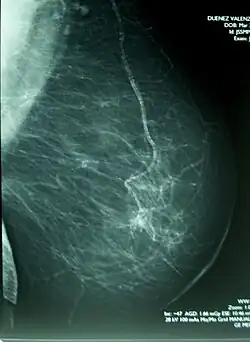

Met een mammografie die gedaan wordt in het kader van bevolkingsonderzoek, of vanwege een verhoogd risico op borstkanker, worden tegenwoordig ook borsttumoren gevonden die verder nog geen klachten gaven.

In Nederland is er een bevolkingsonderzoek waarbij alle vrouwen tussen de 50 en 75 jaar elke twee jaar onderzocht worden op borstkanker. In België bestaat dit onderzoek eveneens tweejaarlijks voor alle vrouwen tussen 50 en 69 jaar. Dit gebeurt door het maken van een röntgenfoto van de borsten, een mammogram. De bedoeling hiervan is borstkanker in een zo vroeg mogelijk stadium op te sporen.

Bij vrouwen met een genetische of familiaire predispositie voor borstkanker geeft de straling die wordt opgelopen bij de mammografie een significant hoger risico op borstkanker.[9] Om deze reden moet bij deze groep extra voorzichtig omgegaan worden met mammografie, met name wanneer zij nog jong zijn.

Hoewel er met een lichamelijk onderzoek, een mammografie, een echo en/of een biopsie vaak al een zeer groot vermoeden op borstkanker kan bestaan, kan de definitieve diagnose pas gesteld worden door de patholoog, wanneer deze borstweefsel dat meestal door een operatie is weggehaald, onder de microscoop kan beoordelen.